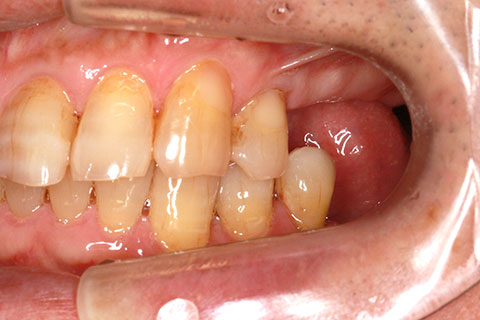

オールセラミックの症例2

- 年齢・性別

- 45歳男性

- 治療期間

- 2ヶ月

- 抜歯

- なし

- 治療費

- 70.4万円

- 備考

- 前歯8本の歯列不正によるセラミック治療

- 治療内容

- 歯質を削除し、セラミック冠をセメント合着

- 施術の副作用(リスク)

- 知覚過敏、歯髄炎、荷重負担